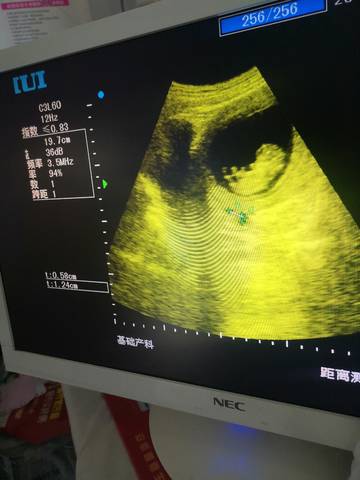

一直流褐色分泌物,b超显示有积液怎么办,图片在下面

上面检查结果有问题,就按照医生的方法来进行保胎,卧床休息,别走动太多,再复查一下

亲爱的,可能就是宫腔积液流出来的一种情况吧,你自己一定要多注意卧床休息呀。

成年女性的阴道呈酸性反应。在个别情况下,阴道和宫颈会有少量的出血。少量的血液在阴道酸的作用下就变成褐色或者咖啡色,流出体外。女性阴道有很多皱襞。有时候一些经血藏匿在皱壁里边,在运动的时候,这些皱襞里的经血残留物又流出来,在酸性的作用下也是褐色的。褐色分泌物都是少量的血。在酸的作用下变成褐色流出来,不是积液流出来了